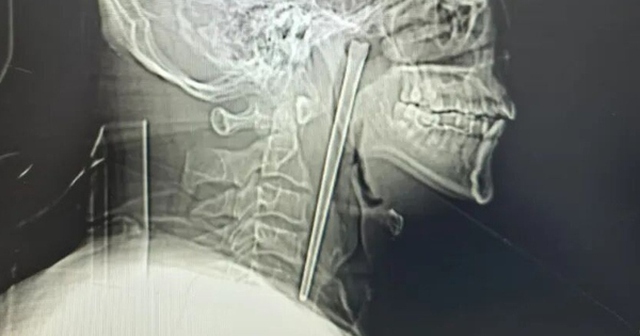

Sau khi kiểm tra, các bác sĩ vô cùng kinh ngạc khi phát hiện một chiếc đũa kim loại dài 12 cm bị mắc kẹt trong cổ họng của người đàn ông.

Các bác sĩ vô cùng kinh ngạc khi phát hiện một chiếc đũa kim loại dài 12 cm bị mắc kẹt trong cổ họng của ông suốt 8 năm qua.

Người đàn ông đau họng dữ dội, bác sĩ lấy ra thứ đáng sợ bên trong- Ảnh 1.

Chiếc đũa được lấy ra khỏi cổ họng người đàn ông.

Nhận thấy có điều gì đó không ổn, Wang vội vã đến bệnh viện. Các bác sĩ phát hiện chiếc đũa kim loại bị mắc kẹt ở phía sau cổ họng của ông, với khoảng 3cm phần đũa nhô ra ở phía trên.

Lần này, các bác sĩ đã tìm ra giải pháp giải quyết được những lo ngại trước đó của Wang và thực hiện một ca phẫu thuật xâm lấn tối thiểu để lấy chiếc đũa ra khỏi miệng ông mà không cần phải rạch cổ. Cuối cùng, chiếc đũa được rút ra nguyên vẹn với rất ít máu chảy ra.